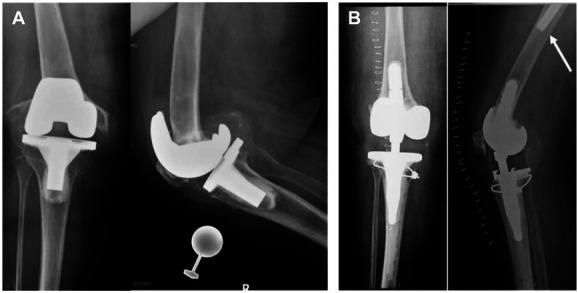

Periprosthetic fractures of the distal femur have significant morbidity in both total hip and total knee arthroplasty (THA and TKA, respectively). The incidence of these fractures is growing, with the predominant mechanism of injury being a fall from a standing height and therefore considered fragility fractures. In many countries, improved public funding and a flourishing private health care sector, when coupled with increased life expectancy, translates to more older patients receiving both TKA and THA and therefore an increased prevalence of periprosthetic fractures and their associated complications. These fractures may occur below a long stem THA, above a TKA, or between the two (so-called "interprosthetic fracture"). We will outline fracture classification, risk factors, diagnosis, and treatment options, highlighting perspectives on treating these fractures in Israel, South Africa, and South Sudan. These countries represent differing access to resources, varied comorbidity factors, and differing health care systems. The points of difference and the points of similarity will be considered.

股骨远端假体周围骨折在全髋关节置换术和全膝关节置换术(分别为THA和TKA)中均具有较高的发病率。这些骨折的发生率正在上升,主要损伤机制是从站立高度跌落,因此被视为脆性骨折。在许多国家,公共资金的改善和蓬勃发展的私立医疗保健部门,再加上预期寿命的延长,意味着更多老年患者接受TKA和THA,从而导致假体周围骨折及其相关并发症的患病率增加。这些骨折可能发生在长柄THA下方、TKA上方或两者之间(所谓的“假体间骨折”)。我们将概述骨折分类、危险因素、诊断和治疗选择,重点介绍以色列、南非和南苏丹治疗这些骨折的观点。这些国家代表了不同的资源获取情况、不同的合并症因素和不同的医疗保健系统。将考虑差异点和相似点。